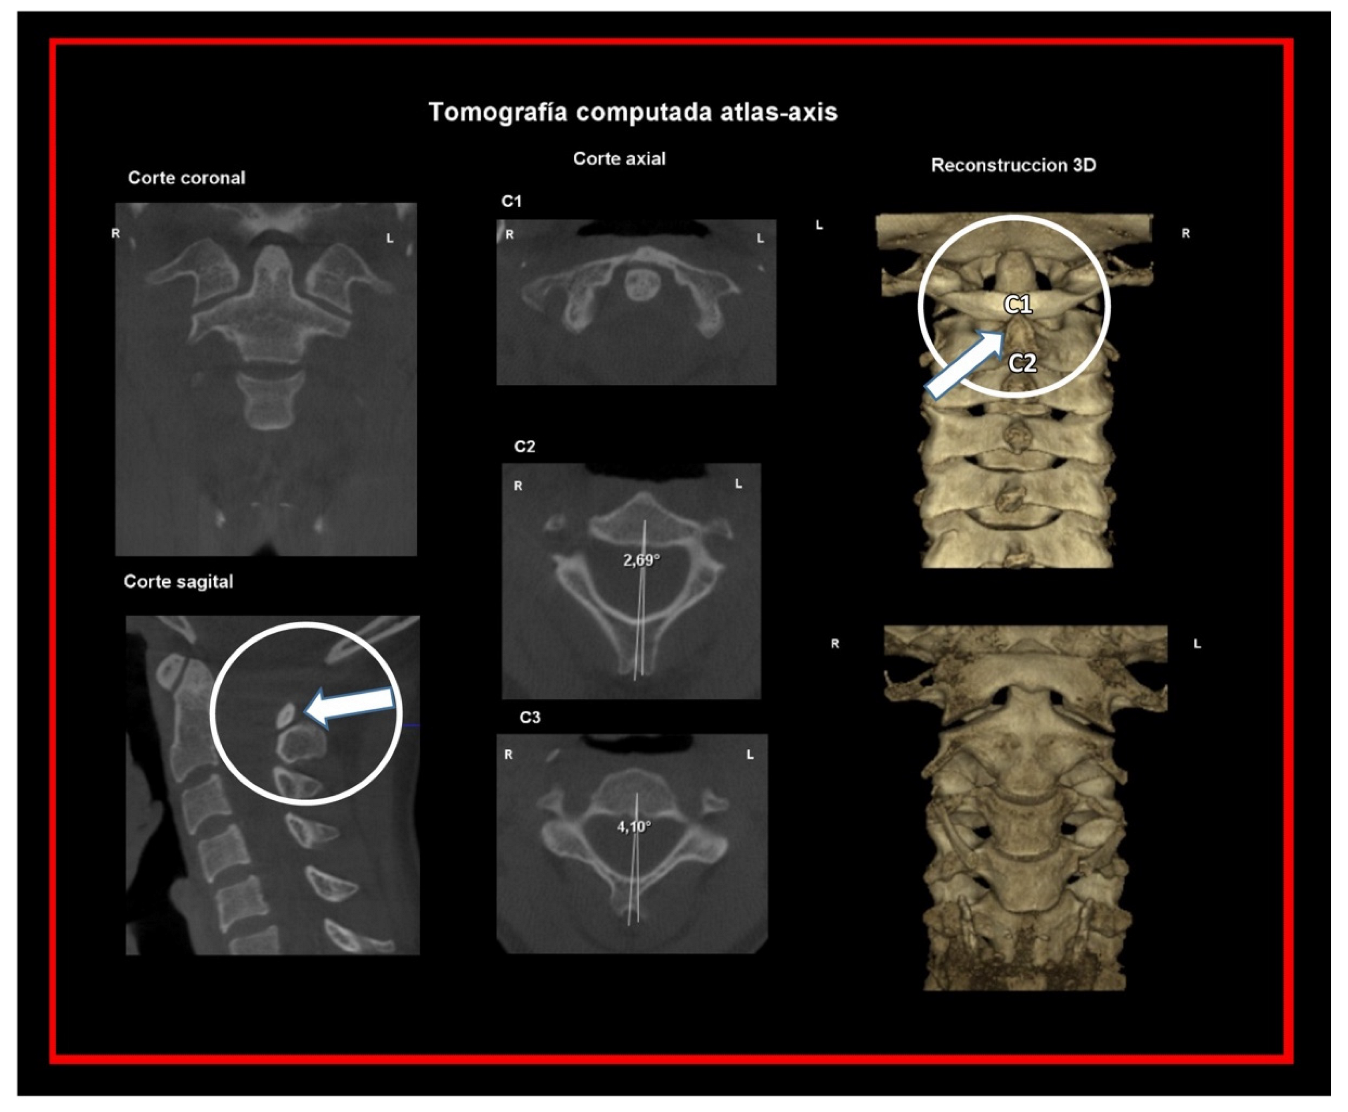

10.2. Computed Tomography of Cervical Spine

11.5. Axis and Atlas Derotation